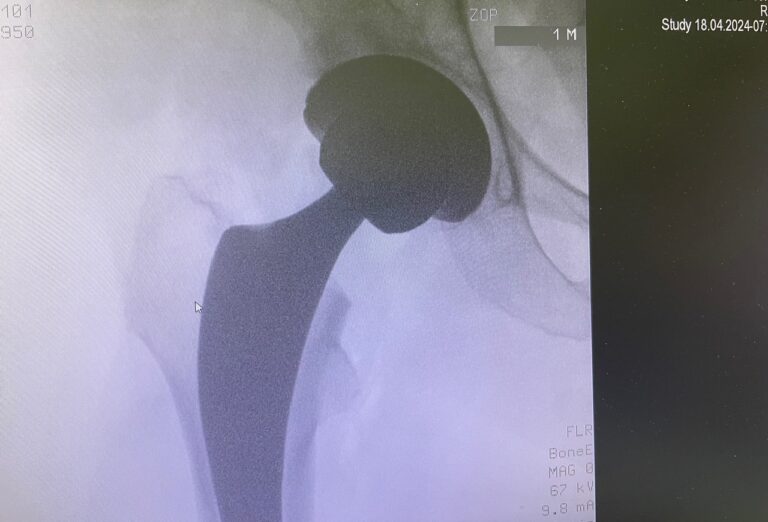

Πώς πραγματοποιείται η επέμβαση

Κατά τη διάρκεια της ολικής αρθροπλαστικής ισχίου:

- αφαιρείται η κατεστραμμένη μηριαία κεφαλή

- τοποθετείται μηριαίο στέλεχος εντός του μηριαίου οστού

- αντικαθίσταται η κοτύλη με τεχνητό κυπέλλιο

- εφαρμόζεται νέα αρθρική επιφάνεια για ομαλή και ανώδυνη κίνηση

Τα εμφυτεύματα είναι κατασκευασμένα από βιοσυμβατά και ανθεκτικά υλικά, όπως τιτάνιο, κεραμικό και ειδικό πολυαιθυλένιο.